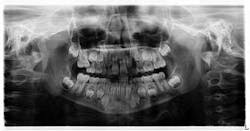

Fig. 4

The following was discussed post-consultation with the orthodontist:

- The mesial drifting of No. 3 was severe enough that it was diagnosed as an irreversible case of ectopic eruption.

- The eruption potential of tooth No. 4 was impeded.

- Leaving the status quo would create a concern for bacterial entrapment and potential abscess; therefore, it was agreed upon that tooth A needed to be removed.